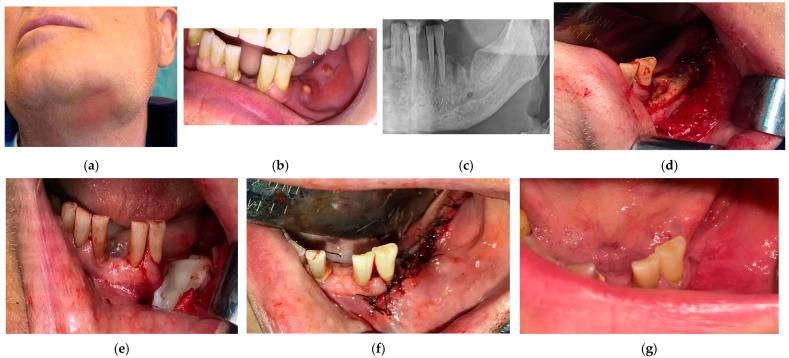

: Antiresorptive or anti-angiogenic agents may induce medication-related osteonecrosis of the jaws (MRONJ), which represents a challenge for clinicians. The aim of this study is to design and apply a composed and stage-approach therapy combining antibiotherapy, surgical treatment, and photo-biomodulation (PBM) for the prevention or treatment of MRONJ lesions. : The proposed treatment protocol was carried out in the Department of Oral & Maxillofacial Surgery of the "Victor Babes" University of Medicine and Farmacy of Timisoara, in 2018-2020. A total of 241 patients who were previously exposed to antiresorptive or anti-angiogenic therapy, as well as patients already diagnosed with MRONJ at different stages of the disease were treated. A preventive protocol was applied for patients in an "at risk" stage. Patients in more advanced stages received a complex treatment. The healing proved to be complete, with spontaneous bone coverage in all the = 84 cases placed in an "at risk" stage. For the = 49 patients belonging to stage 0, pain reductions and decreases of mucosal inflammations were also obtained in all cases. For the = 108 patients proposed for surgery (i.e., in stages 1, 2, or 3 of MRONJ), a total healing rate of 91.66% was obtained after the first surgery, while considering the downscaling to stage 1 as a treatment "success", only one "failure" was reported. This brings the overall "success" rate to 96.68% for a complete healing, and to 99.59% when downscaling to stage 1 is included in the healing rate. Therefore, the clinical outcome of the present study indicates that patients with MRONJ in almost all stages of the disease can benefit from such a proposed association of methods, with superior clinical results compared to classical therapies.

所提议的治疗方案于2018年至2020年在蒂米什瓦拉“维克托·巴比什”医科大学口腔颌面外科实施。共有241名先前接受过抗吸收或抗血管生成治疗的患者,以及已在疾病不同阶段被诊断为MRONJ的患者接受了治疗。对处于“风险”阶段的患者应用了预防方案。处于更晚期阶段的患者接受了综合治疗。结果证明愈合是完全的,处于“风险”阶段的所有84例患者均实现了骨的自发覆盖。对于属于0期的49例患者,所有病例均实现了疼痛减轻和黏膜炎症减轻。对于提议进行手术的108例患者(即处于MRONJ的1、2或3期),首次手术后的总愈合率为91.66%,而将病情降级至1期视为治疗“成功”的话,仅报告了1例“失败”。这使得完全愈合的总体“成功”率达到96.68%,若将病情降级至1期纳入愈合率计算,则为99.59%。因此,本研究的临床结果表明,几乎所有疾病阶段的MRONJ患者都可从这种提议的联合治疗方法中获益,与传统疗法相比临床效果更佳。